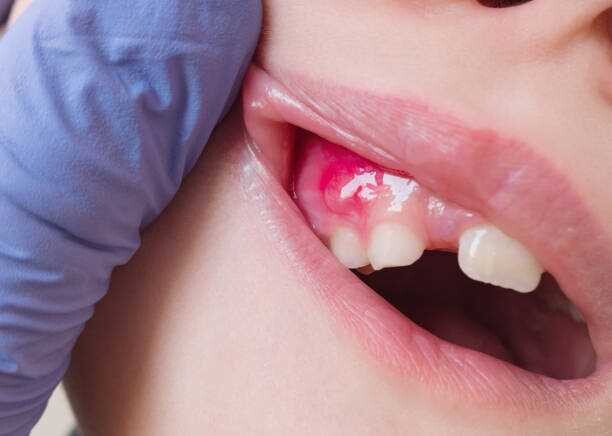

Gingivitis/ Gum DiseaseGingivitis is a first stage of gum disease and needs and needs early intervention or it can progress further into bone loss and eventually loss of teeth. The symptoms of gum disease include red and swollen gums that bleed easily.

Care – Follow your routine teeth care and visit your dentists regularly for oral check-up and cleaning.